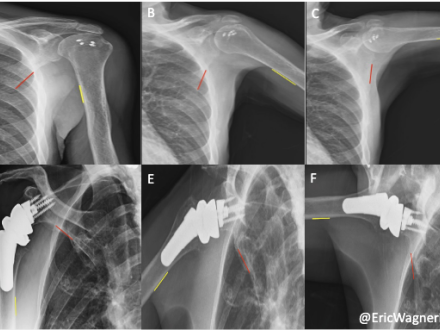

Wayne, NJ, May 27, 2025 – Konica Minolta Healthcare Americas, Inc., congratulates Emory Healthcare researchers on the publication of a new study using Dynamic Digital Radiography (DDR) to compare shoulder biomechanics in patients after two widely accepted surgical interventions for massive irreparable rotator cuff tears (MIRCTs). Reverse shoulder arthroplasty (RSA) and arthroscopically assisted lower trapezius tendon (aLTT) transfer are often used to repair these tears, however, quantifying shoulder function post-operatively has remained difficult to assess. However, with the use of novel DDR imaging, it provided the ability to examine in-vivo kinematics by measuring scapulohumeral rhythm (SHR), the ratio of the glenohumeral and scapulothoracic contributions to shoulder motion, non-invasively in patients. The authors also aimed to design an objective methodology for selecting the appropriate intervention that will maximize the patient’s shoulder mobility with the help of DDR. The study is in press and available online in the Journal of Shoulder and Elbow Surgery.

DDR is a novel, low-dose X-ray imaging technique available on Konica Minolta Healthcare DR Systems that captures both static images and cinegrams, providing an innovative way to obtain detailed images of complex joints like shoulders while in motion. By acquiring a series of images at high speed, DDR generates a cineloop that enables clinicians to visualize anatomical motion over time (cineradiography), enhancing the system’s diagnostic capabilities.

Utilizing DDR to characterize scapulohumeral rhythm both pre- and post-operative and evaluate for precise changes in SHR, Sameer R. Khawaja, MD, and collaborators, including the leadership of Eric R. Wagner, MD, MSc, and his research lab, demonstrate that Dr. Wagner’s patients undergoing aLTT yields superior restoration of shoulder biomechanics for patients suffering from MIRCTs than his patients undergoing RSAs. The study highlights how aLTT transfer enhances shoulder stability and improves functional mobility. In contrast, RSA is a very successful treatment of MIRCTs and other pathologies but fails to restore the same level of native biomechanics as the aLTT.